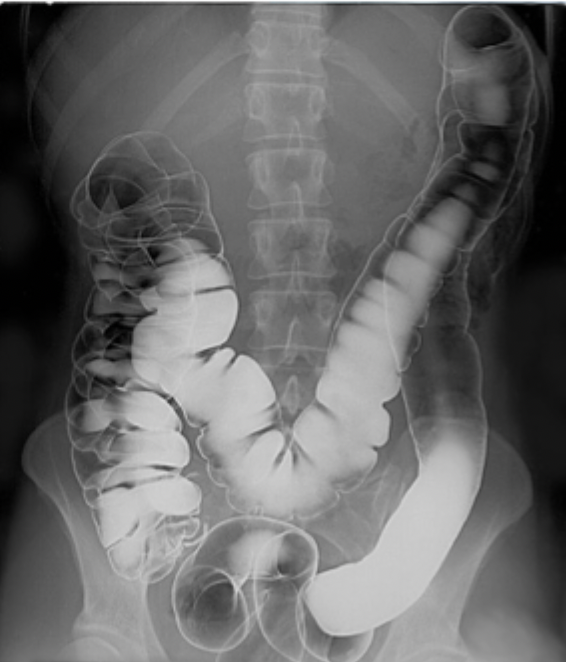

Contrast enhanced image

Barium and gas added

Lumen can be seen well

Double contrast as barium can close up the tube so gas is added afterwards to mimic the natural shape of the large intestines

Barium based contrast media

Orally ingested for barium swallow (pharynx, oesophagus and stomach) and barium follow through (duodenum, jejunum and ileum) or rectally instilled for barium enema (large intestines, rectum and anus - find tumours and distension

Commonly added with gas to inflate the bowels - called double contrast